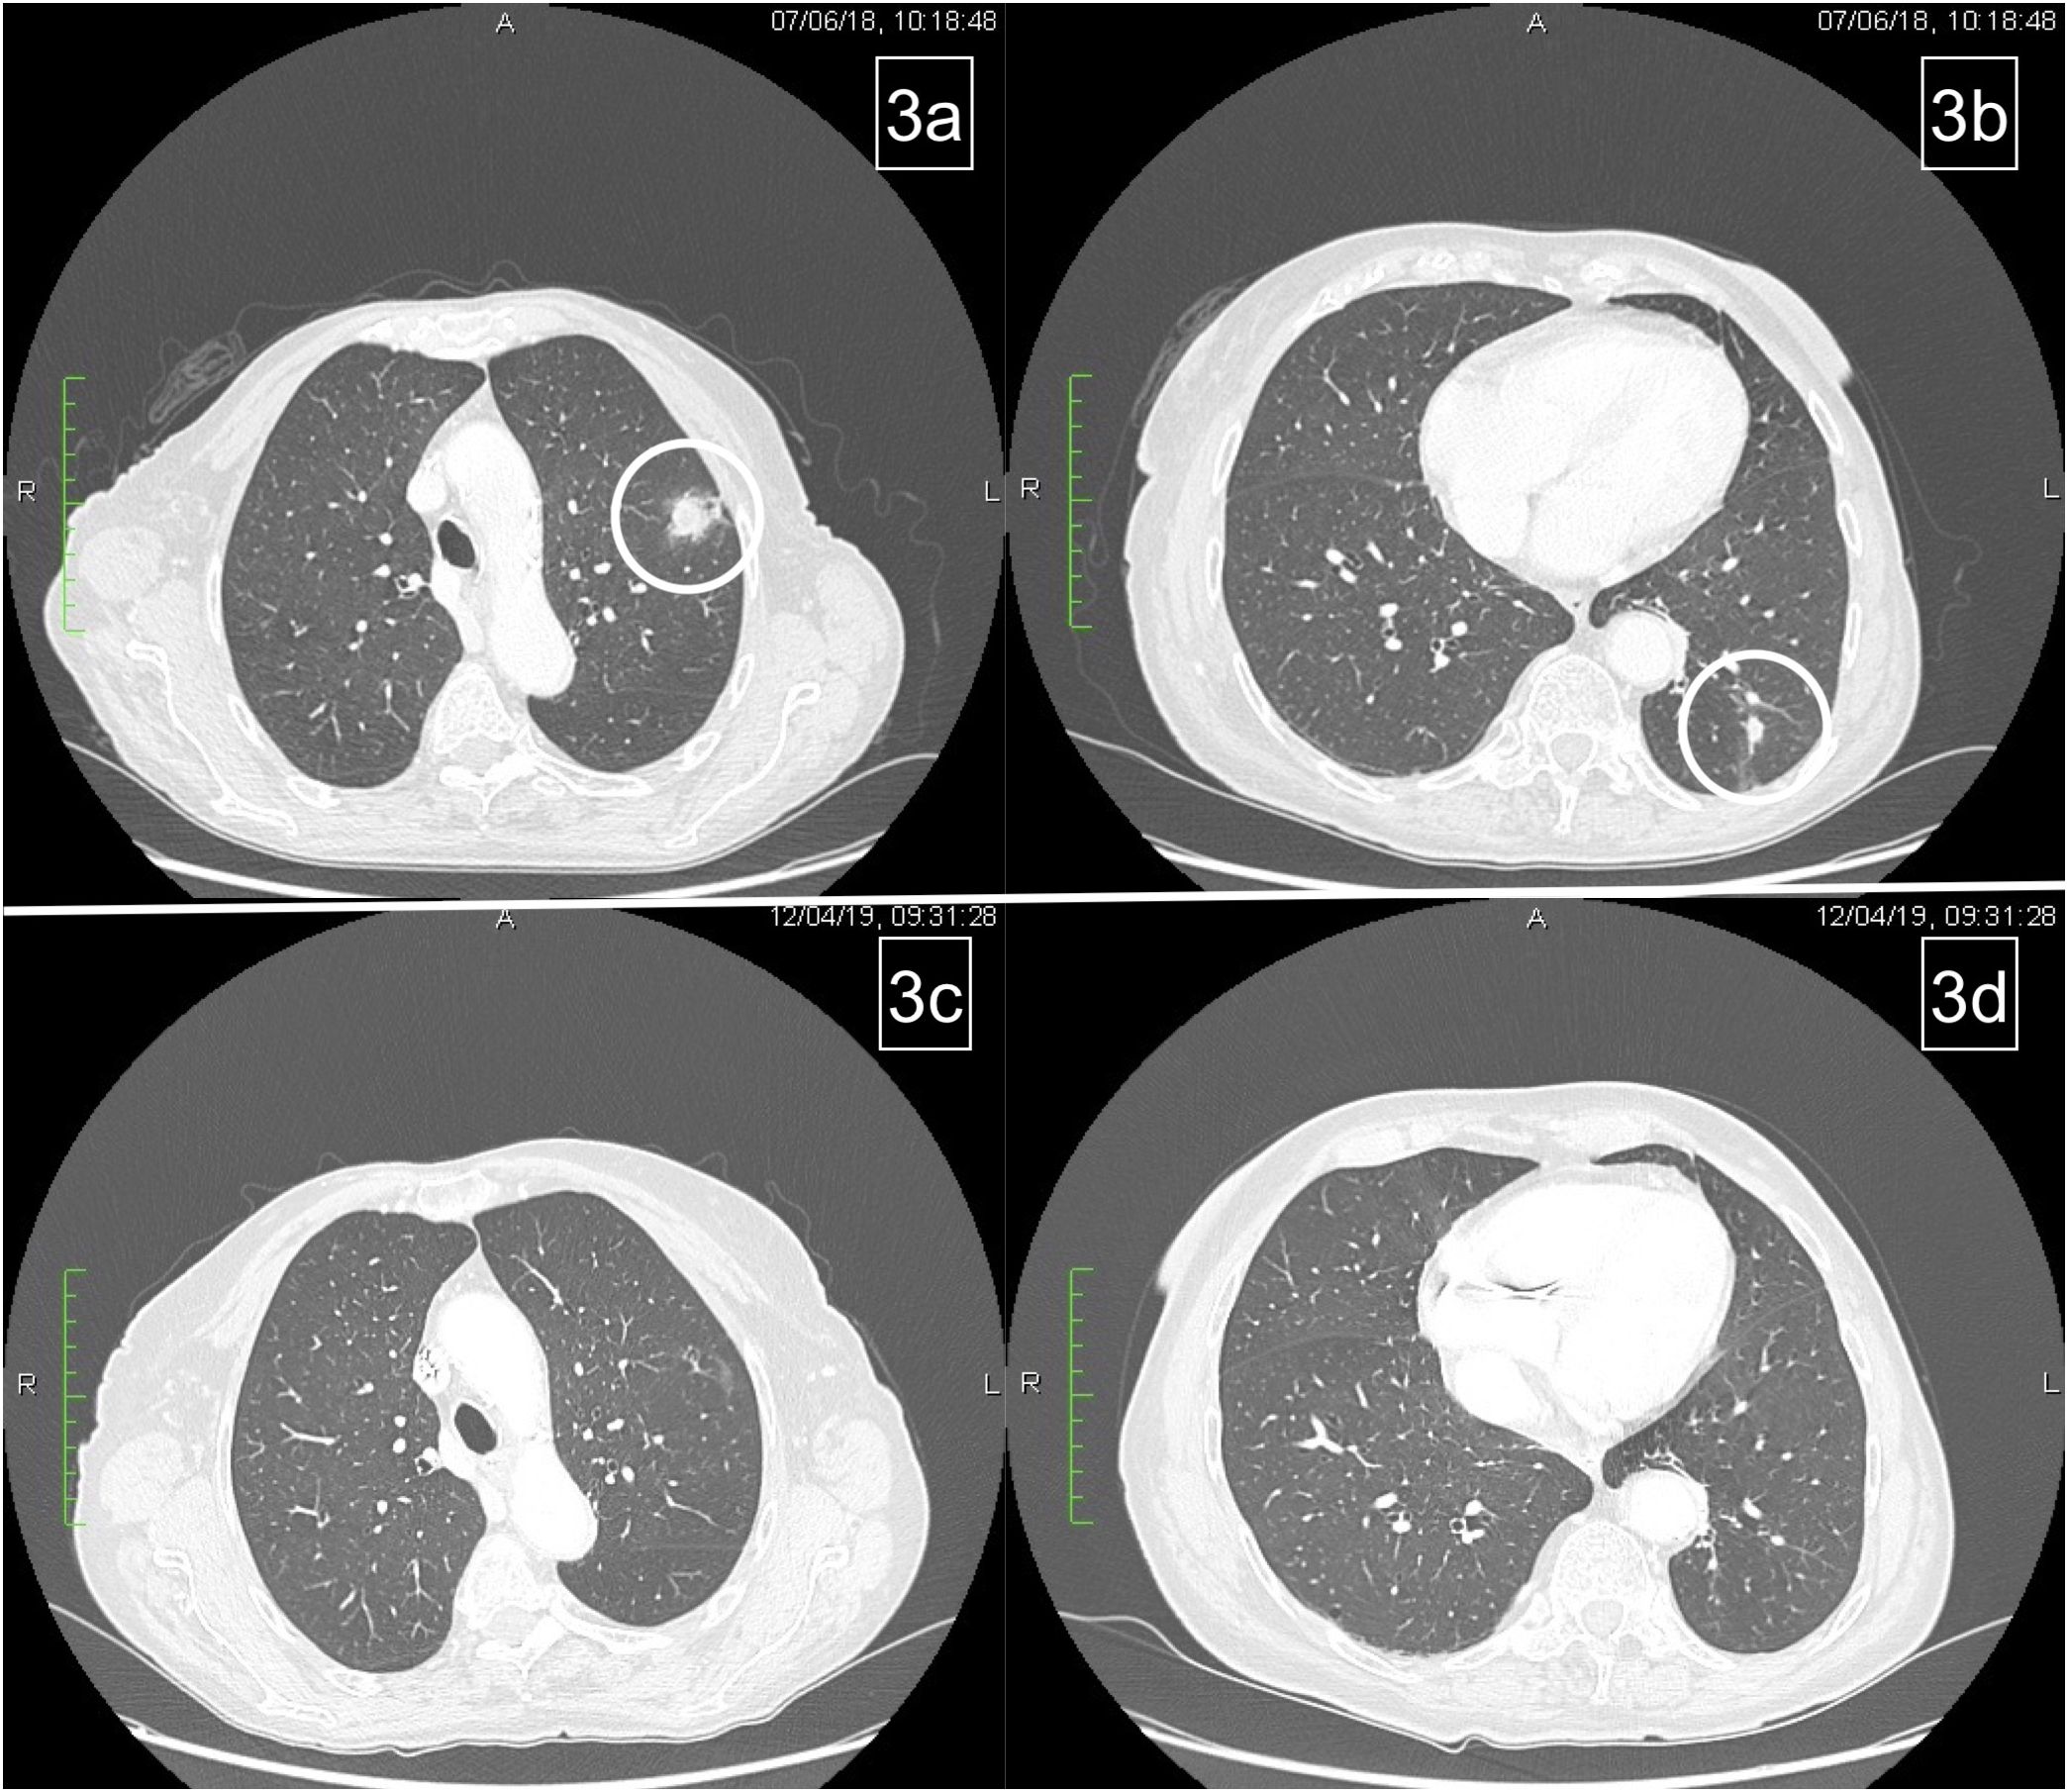

Figure 2 Basal metastatic sites at diagnosis: primary tumor (PT), left axillary node (AN), pleural nodes (PlN), and peritoneal node (PeN) (A–D). Response to treatment after six courses: patient achieved response on primary tumor and all metastatic sites, except for the left axillary node (E–H).

In January 2017, the patient began chemotherapy with mFOLFOX-6 plus panitumumab. After six cycles, she reported a mixed response for a partial remission on metastatic sites but progressive disease on the axillary node (Figures 2E–H). During these first 3 months, the patient reported G1 skin rash, G1 peripheral neuropathy, and G2 neutropenia as side-effects, according to CTCAE 4.0.

This case was evaluated by a multidisciplinary team. Since disease progression only occurred at a single site, surgical excision of the left axillary node was scheduled (April 2017). Histopathological findings were compatible with metastasis from intestinal adenocarcinoma and the molecular assessment detected a BRAF V600E mutation that was probably the cause of resistance to panitumumab.